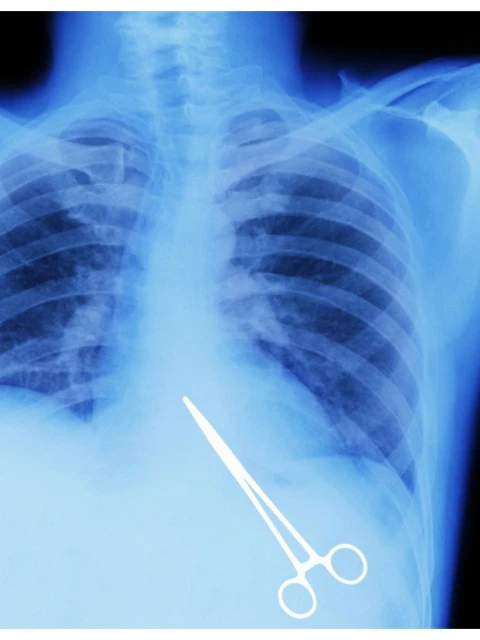

Hasta hace unas semana su vida era normal, hasta que comenzó a sentir molestias y fuertes dolores que le comenzaron a incomodar en la parte donde había sido operado hace ya cinco años. Al realizarse estudios, más precisamente una placa radiográfica, la sorpresa fue grande para quienes hacían los estudios al comprobar que en el interior del hombre había una tijera quirúrgica que habría quedado allí durante su operación.

El insólito hecho le ocurrió a un hombre, oriundo de Los Antiguos en la provincia de Santa Cruz, quién hace cinco años había sido operado tras sufrir un violento accidente de tránsito. Sufrió graves lesiones, entre ellas varias costillas fracturadas y lesiones en el bazo, por lo que requirió cirugía para poder extirpárselo.